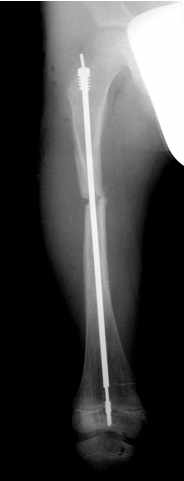

Teleskopnagelung in der Osteogenesis imperfecta-Behandlung

Bei der operativen Behandlung steht die Versorgung von Knochenbrüchen oder Achsfehlstellungen mit Teleskopnagelungen im Vordergrund. Aus orthopädischer Sicht ist trotz ständiger Bruchgefahr viel Bewegung wichtig, um eine stützende Muskulatur aufzubauen und Skelettveränderungen vorzubeugen bzw. zu verzögern.